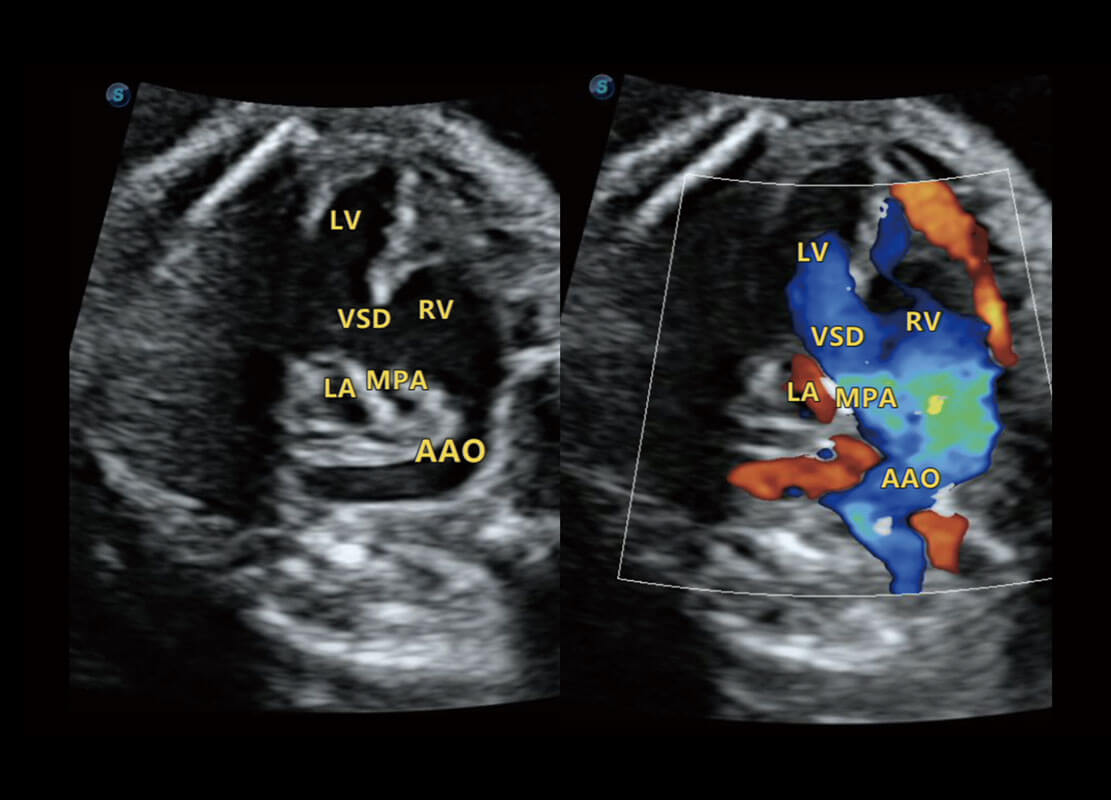

P60搭载一系列胎儿心脏成像技术,实现精细的胎儿心脏评估。

• 右室双出口